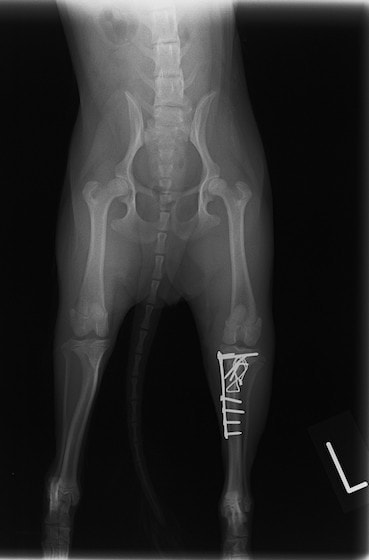

症例3:キルシュナーワイヤーのピンニングによる整復

ペルシャ猫 11ヶ月齢 雄

他院にて左大腿骨遠位の成長板骨折(salter-harrisⅠ型)が認められており、治療相談を目的として来院。当院にて、キルシュナーワイヤーを用いたピンニングにより骨折部位の整復を行いました。術後の経過は良好で、現在も経過観察中です。

術前レントゲン

術後レントゲン